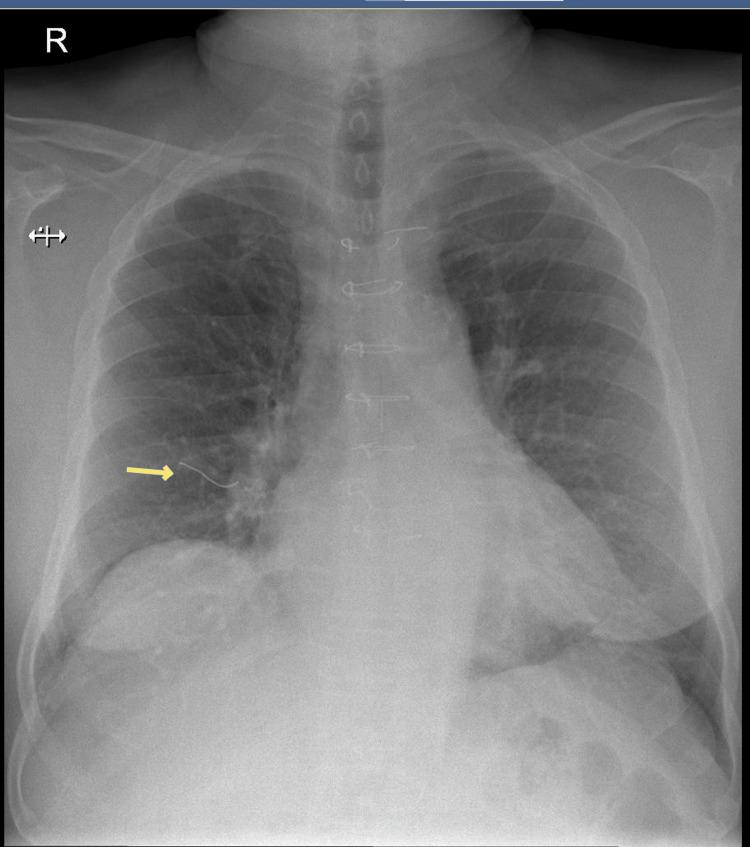

Sternal wire displacement is a rare but important postoperative complication following median sternotomy, commonly performed during cardiothoracic surgeries, such as coronary artery bypass grafting (CABG). While wire breakage and migration are known, migration into the deep subcutaneous plane without involvement of intravascular or muscular structures is extremely uncommon. We report a 71-year-old male with a history of triple vessel disease status post CABG 12 years prior, presenting with acute dyspnea. Imaging revealed pulmonary edema and an incidental finding of a migrated sternal wire in the deep subcutaneous plane anterior to the pectoralis major. Serial chest X-rays demonstrated gradual disruption and migration of the lowermost sternal wire over several years. The patient remains asymptomatic regarding the wire migration and is being managed conservatively with regular follow-up. This case highlights an unusual presentation of sternal wire migration confined to the subcutaneous plane, emphasizing the importance of long-term radiological surveillance in post-sternotomy patients. Although often asymptomatic, displaced sternal wires may pose significant risks, necessitating individualized management strategies. Conservative monitoring with periodic imaging is a reasonable approach when the patient is asymptomatic and the wire is stable.

https://cdn.ncbi.nlm.nih.gov/pmc/blobs/2903/12460196/00b182b10fd5/cureus-0017-00000090915-i01.jpg